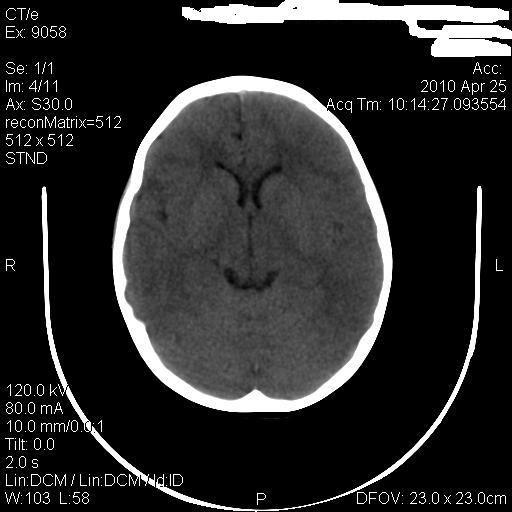

标题: PED3218:3岁女孩,曾有外伤史。未提供前片 [打印本页]

标题: PED3218:3岁女孩,曾有外伤史。未提供前片

发育略有障碍。欢迎大家发言。谢谢!

考虑右侧额顶叶脑软化灶并脑穿通畸形。

考虑:1)右侧额顶叶脑软化灶并脑穿通畸形。2)胼胝体发育不良。

支持考虑:1)右侧额顶叶脑软化灶并脑穿通畸形。2)胼胝体发育不良。

1)右侧额顶叶脑软化灶。2)胼胝体发育不良?

考虑右侧额顶叶软化灶并脑穿通畸形,胼胝体发育不全。

还有脑室周围白质软化症